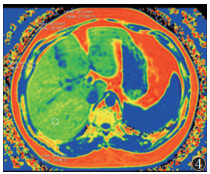

68例采用Philips Prodiva 1.5 T MRI扫描仪,行mDixon-Quant序列扫描。受试者取仰卧位,线圈中心与剑突下缘平齐,呼吸门控软管置于腹前壁正中,呼气末屏气扫描获取图像。扫描参数:Scan mode 3D,TR 6.5 ms,TE 1.15 ms,视野375 mm×297 mm×201 mm,体素3.00 mm×3.02 mm×6.00 mm。后经自动重建、靶区勾画等步骤计算各肝段PDFF值,选取肝Ⅴ段PDFF值作为最终观察指标(图 4)。操作时注意避开大血管、胆管、病变、伪影等的干扰。

| 注:测量肝Ⅴ段PDFF值 图 4 肝脏MRI质子密度脂肪分数(PDFF)图 |